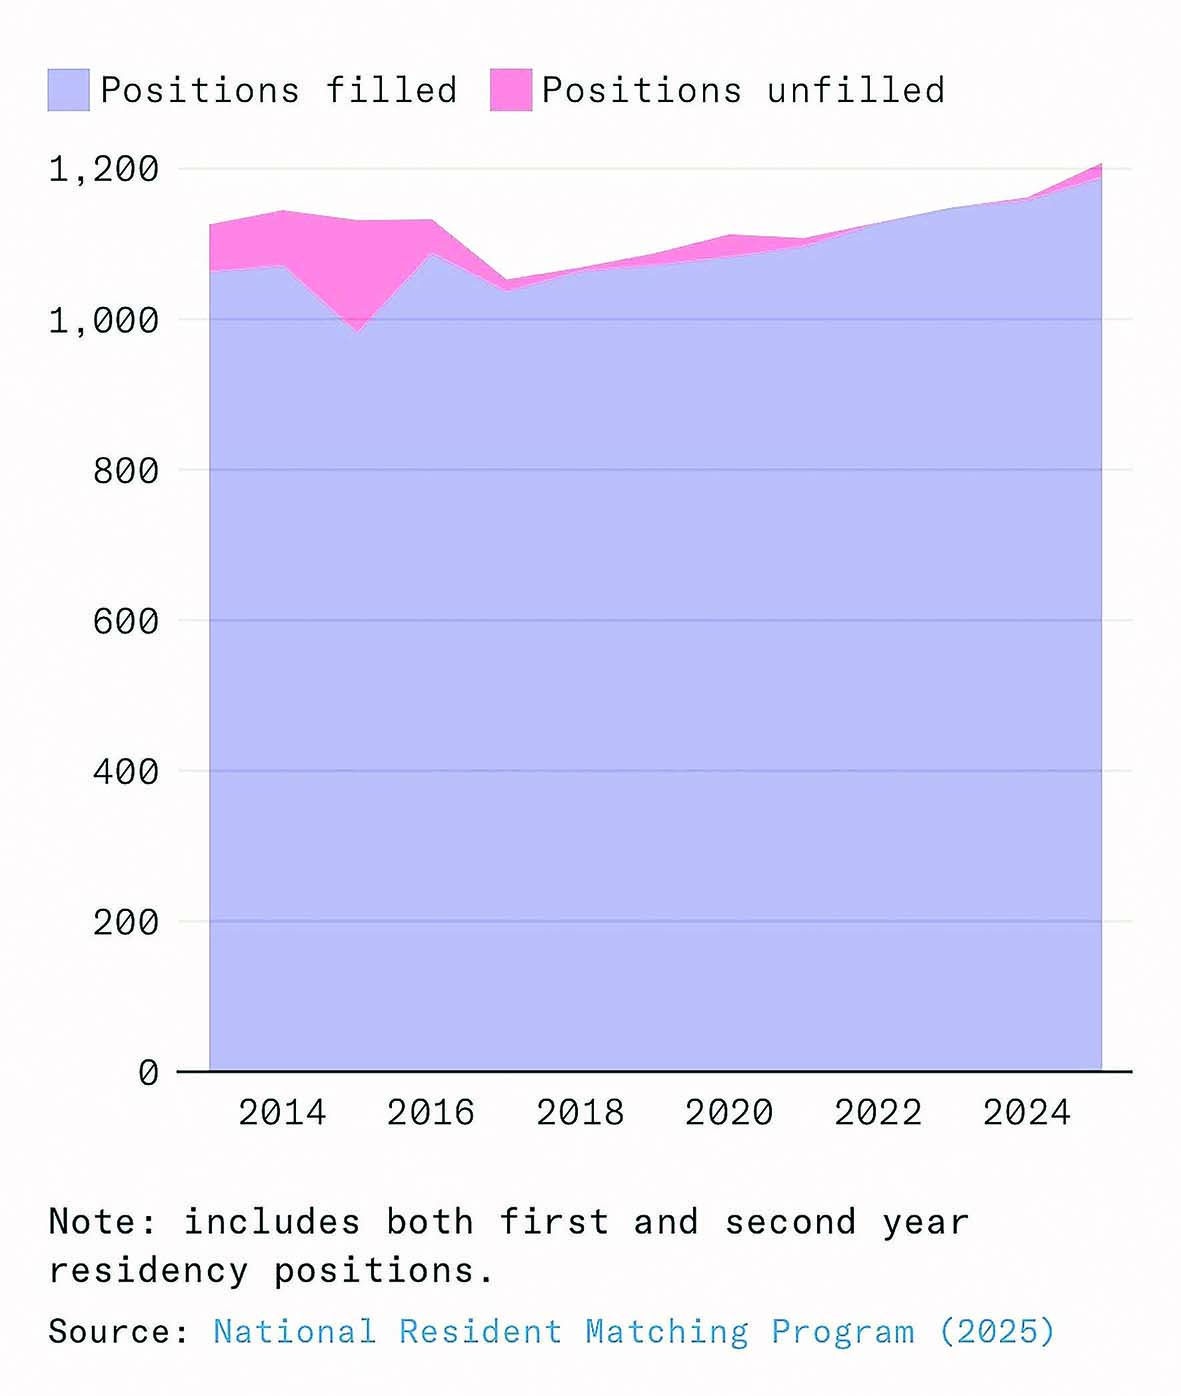

رادیولوژی حوزهای است که برای جایگزینی نیروی انسانی بهینهسازی شده است؛ جایی که ورودیهای دیجیتال، وظایف مبتنی بر تشخیص الگو و شاخصهای روشن غالب هستند. در سال ۲۰۱۶، جفری هینتون، دانشمند رایانه و برنده جایزه تورینگ اعلام کرد که «از همین حالا باید آموزش رادیولوژیستها را متوقف کرد.» اگر افراطیترین پیشبینیها درباره اثر هوش مصنوعی بر اشتغال و دستمزدها درست بود، آنگاه رادیولوژی باید مانند قناری در معدن زغالسنگ عمل میکرد و اولین نشانههای خطر را نشان میداد اما تقاضا برای نیروی انسانی بیش از هر زمان دیگری است. در سال ۲۰۲۵، برنامههای رزیدنتی رادیولوژی تشخیصی آمریکا رکورد ۱۲۰۸ موقعیت رزیدنتی را در تمام تخصصهای رادیولوژی ارائه دادند؛ افزایشی ۴درصدی نسبت به سال ۲۰۲۴. نرخ خالی بودن جایگاهها در این حوزه نیز به بالاترین سطح تاریخ خود رسیده است. در سال ۲۰۲۵، رادیولوژی دومین تخصص پردرآمد پزشکی در ایالات متحده بود، با درآمد متوسط ۵۲۰هزار دلار، یعنی بیش از ۴۸درصد بالاتر از میانگین سال ۲۰۱۵.